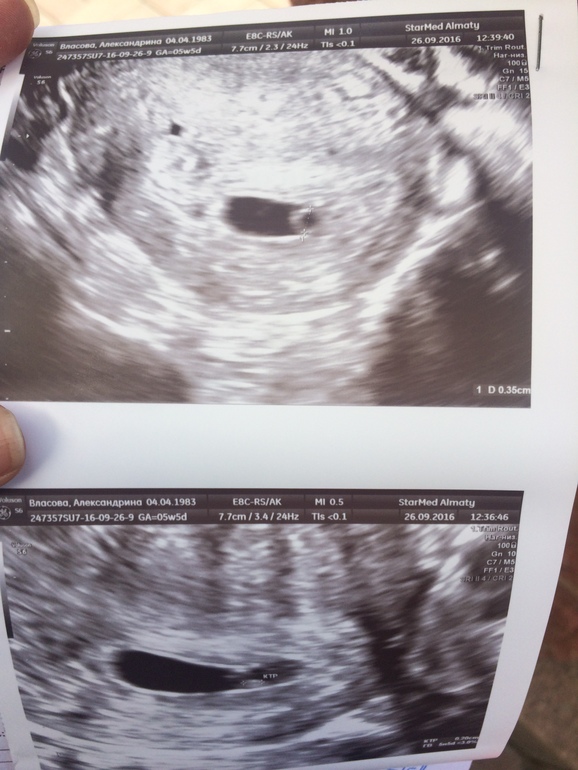

Очередной приём у Г принёс хорошие новости о низких рисках по крови на скрининге 1 триместра ☺️☺️👍🏻

Все прекрасно, все соответствует сроку!